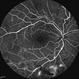

- Proliferative Diabetic Retinopathy with Subhyaloid Hemorrhage

- subhyaloid hemorrhage, retinal neovascularization, ischemia

- 43 year old diabetic man with proliferative diabetic retinopahty, subhyaloid hemorrhage, ischemia, neovascuarization.